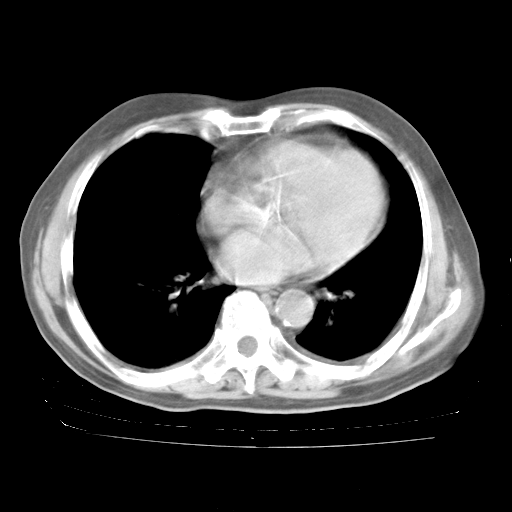

4月28日肺部CT

个人阅读4.14日肺部CT平扫:纵隔窗无异常,但肺窗示:双下肺内、后基底段有片絮状侵润影,部位以后基底段为著,以间质改变为主,呈急性肺泡炎征像,和首次住院影像学有相似之处。仅是个人读片,明日请相关专家再读片哈。其它建议同上。

1、108#的是4月14日的胸部CT(发此贴时还没看着28日的CT)。14日的胸部CT其实已经出现改变(如108#所述),个人认为28日的胸部CT除纵膈窗疑似有双侧胸膜增厚或少量胸积液(可行胸部B超明确)外,与4月14日对照病变有所加重;2、已经给予“异烟肼、利福平、乙胺丁醇”抗痨治疗?如果是,甲强龙80mg可缓慢减量;如果环磷酰胺已停用,暂不使用;3、中性粒细胞92%,明显升高,目前体温情况?注意合并细菌感染可能,使用左氧氟沙星情况下,是否联用B-内酰胺类抗菌药物?另外是查免疫全套非风湿全套。